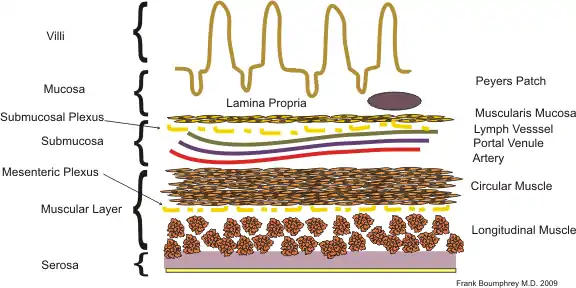

The GI tract is essentially a hollow tube connecting the mouth to the anus. The GI tract has a similar layout through out its length:

- An inner mucosal layer with an epithelial lining

- A submucosal layer

- A thin layer of muscle , the Muscularis Mucosa is at the junction of the mucosal and sub mucosal layers, outside this are the nerves of the mucosal plexus

- A muscular layer with an inner circular muscle layer and an outer longitudinal layer

- Between the muscles are the nerves of the myenteric plexus

- A serosal layer which is continuous with the mesentry

This is illustrated graphically here:

The mucosal layer consists of a epithelial layer, and its underlying supportive tissue, the Lamina Propria. It is separated from the submucosal layer by the Muscularis Mucosa. The epithelial layer varies from section to section of the gut. In the oesophagus it is a non-cornified stratified squamous epithelium; in the stomach it is mainly mucosal cells; the small intestine and large intestine are characterized by absorptive cells, with many mucous producing goblet cells. In the absorptive sections of the intestine, the surface are for absorption is greatly increased by finger-like projections into the lumen called villi, and the absorptive cells themselves also have small projections of microvilli, giving them the appearence of a brush border when viewed with a light microscope.

The lamina propria contains lymph and blood vessels which drain into larger vessels in the submucosal layer. Also in the lamina propria, particularly in the absorptive layers are numerous immune cells, wandering macrophages and lymphocytes, as well as aggregations of lymphoid tissue called called Peyers patches. By some estimates 80% of the body's lymphoid tissue is in the intestine.

Submucosa

The submucosa consists of connective tissue with larger blood and lymph vessels. It is separated from the mucosa by the muscularis mucosa. Also in the submucosal layer is the submucosal plexus, part of the enteric nervous system. The muscularis mucosa probably acts to propel the contents of the mucosal glandular lumens and crypts (see below) into the lumen and also to enhance contact of the cells with the contents of the lumen.

Muscular Layers

Consists of an inner circular muscle, and an outer longitudinal muscle. Between the two layers is the mesenteric plexus, also part of the enteric nervous system. In the stomach there is also an oblique layer of muscle fibers interior to these two. The musclar layers work in harmony to produce peristaltic contractions and segmental contractions.

Serosa

The serosa is a continuation of the peritoneal membrane. It is useful to think of the gut as being envaginated into the peritoneal membrane until it completely surrounds it. The double layer of membrane as it attaches to the gut is called the mesentery, and it contains the main vessels and the non-intrinsic nerve supply to the gut.

The small intestine, where most of the absorption occurs, is divided into three sections, the duodenum, the jejunum, and the ileum. In all three sections the layers follow the general pattern:

The surface for absorption is increased in many ways: the mucosa of the small intestine is thrown into folds called rugae; the mucosa itself has numerous finger-like projections called villi, and the epithelial cells are also covered with numerous projections called microvilli. The microvilli give the appearance of a 'brush' on light microscopy; hence the term brush border. The following illustration shows the anatomy of a villi:

Mucous is secreted by numerous goblet cells; other cells are specialized for absorption and are known as absorptive cells. In the base of the crypts are numerous secretory cells which secrete the digestive enzymes of the small intestine. Some of the crypts penetrate into the submucosal layer, forming digestive glands which will communicate with the mucosa via a secretory duct.